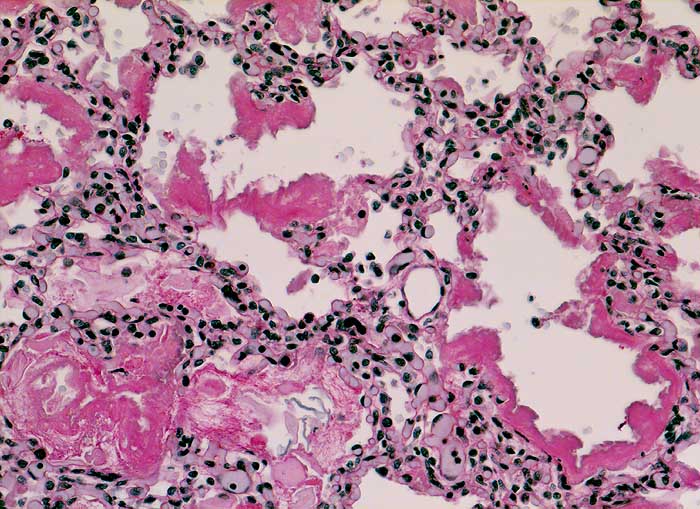

PathoPic ID 6177 - Hyaline Membranenkrankheit (IRDS)

Hyaline Membranenkrankheit (IRDS)

Massive Mekoniumaspiration:

Mekonium in einzelnen Alveolarräumen. Die Alveolarsepten sind austapeziert von PAS positiven

hyalinen Membranen.

Normalgewichtiges Neugeborenes der 37. SSW. Linksbetonte Hypoplasie beider Lungen. Lungen vor allem im alveolären Stadium.

Kongenitale beidseitige Diaphragmahernie bekannt seit 24. Schwangerschaftswoche.

Asphyxie bei Hypoplasie beider Lungen.

Histologie

100